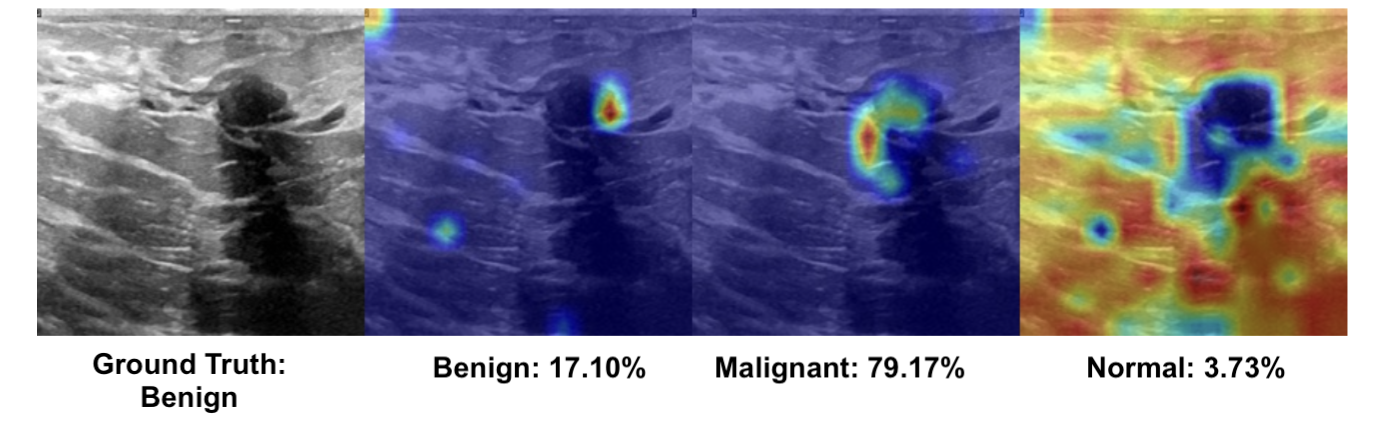

3.4.1 Qualitative Error Analysis

When a model is explainable, its visual attributions—such as Grad-CAM heatmaps—can provide insights into the reasoning behind incorrect predictions. Figure 4 shows two such cases by the DINO-ViT model. In the PBC example (top), the model predicted the class as Immature Granulocyte with 67.43% confidence, while the ground truth label is Monocyte. The Grad-CAM heatmap for the predicted class shows strong activation around the nucleus, suggesting the model misinterpreted the shape and granularity as irregular features typical of Immature Granulocyte cells, which led to the misclassification. Meanwhile, the heatmap for the true class displays weaker and more diffused attention, suggesting that the model has not learned a sufficiently strong representation for Monocyte. The activation patterns observed across other classes further demonstrate how subtle visual similarities can lead to confusion in fine-grained classification tasks.

In the breast ultrasound example (bottom), the model misclassified a Benign lesion as Malignant with 79.17% confidence. The heatmap for the predicted class highlights the central lesion area with strong intensity, indicating that the model focused on structural features associated with malignancy, such as asymmetry or irregular margins. Meanwhile, the heatmap for the true class appears weaker and less defined, suggesting the model failed to learn sufficiently discriminative features for benign cases. These examples demonstrate that explainability methods like Grad-CAM can reveal the underlying reasons behind model misclassifications, offering valuable insights for diagnosing and improving model behavior.